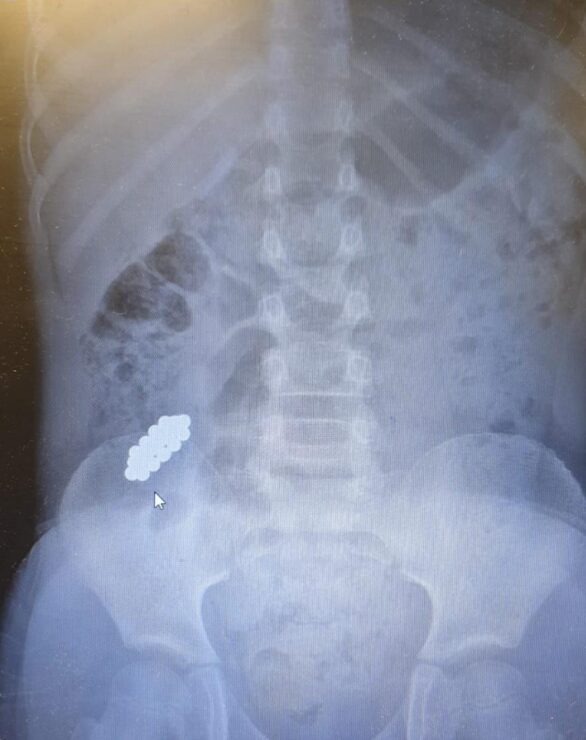

ד"ר אייל זיפמן, מנהל השירות לגסטרואנטרולוגיה ילדים מסביר כי בגלל ההבנה לגבי הנזק שמגנטים עלולים לחולל – והחשש מנקב במעי וזיהום בחלל הבטן, הוחלט לשלוח את הילד באופן מידי לצילום. בצילום נצפו המגנטים במעי הדק במקום שלא ניתן להגיע ללא ניתוח. הוחלט כי נעשה מעקב לבחון את מקומם ובשלב מסוים נמצא כי הם אינם מתקדמים לבד ויש לעשות קולונוסקופיה. המגנטים נמצאו במעי הגס והוצאו בהצלחה".